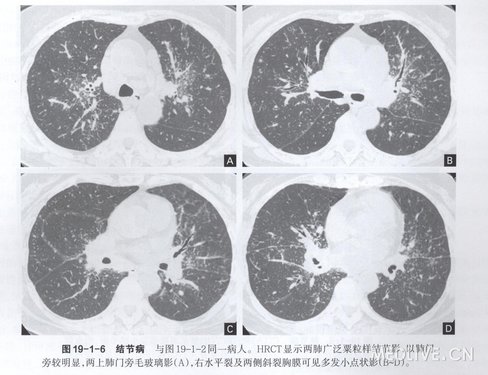

2.CT表现双侧肺门淋巴结对称性肿大为最典型的CT表现(图19-1-3)。另外,病变早期,非特异性间质性肺泡炎在CT上表现为斑片状阴影或毛 玻璃样改变,肺实质可见云雾状的轻度密度增高影(图19-1-4),其内的血管和支气管隐约可见;病变进一 步发展所形成的非干酪性肉芽肿,在CT上表现为沿血管和支气管走行分布的粟粒状结节影(图19-1-5),直径多为1—5 mm,边缘光滑;非干酪性肉芽肿也可位于肺外围、小叶间隔或斜裂附近的胸膜下,表现为血管、支气管串珠状增粗及小叶间隔串珠状增厚(图19 -1-6)。因此,在HRCT上,结节病的肺内粟粒样结节影沿淋巴道分布,即沿支气管血管束、 小叶中心、小叶间隔及胸膜面分布。粟粒样结节影的分布通常呈两侧对称性,但也可呈以单侧分布为主(图19 -1-7)。结节病肺内也可见小结节影(图19 -1-8),部分可发生融合形成较大结节影。当云雾状斑片影和结节影同时出现时,常提示活动性肺泡炎向肉芽肿过渡。病变晚期,间质纤维化形成,CT 表现为小叶结构扭曲、肺门及斜裂移位、牵张性支气管扩张移位及网状致密影等。CT还有助于追踪观察,以判断疗效(图19 -1-9)。